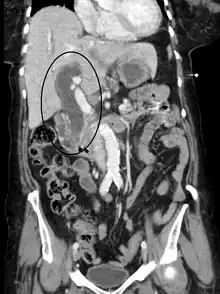

| Jaundice caused by pancreatic cancer | |

Post-hepatic jaundice (obstructive jaundice), is caused by a blockage of bile ducts which transport bile containing conjugated bilirubin out of the liver for excretion. The following is a list of conditions that can cause post-hepatic jaundice:

- Pancreatic cancer of the pancreatic head